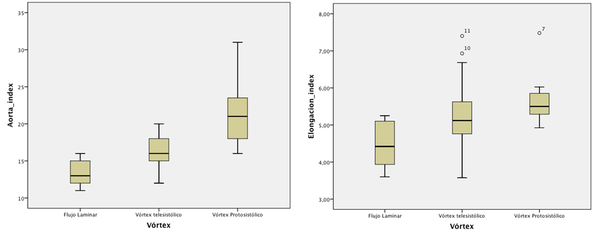

4D Phase Contrast Cardiac Magnetic Resonance(4D-PC-CMR) sequences allow to obtain three-dimensional flow images (see section 1.4.1.1) and to analyze of the patient-specific characteristics of intravascular flows under normal and pathological conditions. In clinical practice, these sequences allow to advance the understanding of the pathophysiology of vascular diseases through the interaction between flow and anatomy. Besides of this, it also help to understand the origin of diagnostic errors of 2D flow PC sequences. The aim of this study is to describe and characterize qualitatively different patterns of systolic flow in the Ascending Aorta(AoAsc) against to its aortic diameter with different degrees of root dilatation and against the different aortic valve pathologies using 4D PC Cardio MR sequences.All the patients (31 patients) who participated in this trial were volunteered and provided written consent to be part of this study. This study was reviewed and approved by the Ethics Committee of the Hospital Sant Pau i Creu Blanca, Barcelona, Spain. The 31 patients have different aortic problems, 12 patients suffer cardiomyopathy, 6 patients have a dilated aorta, 4 patients have aortic valve disease, 1 patient has a mitral valve disease, 1 patient has an atrial fibrillation and another suffers syncope, as well as 5 were healthy volunteers. For each patient an anatomy/flow cross-sectional of AoAsc was done. The flow pattern studied was: (i) at the Valsalva sinus (SV), where the flow adopts a uniformity velocity with a peak in the middle of the aorta (see figure 11.A and 11.B) or an eccetric flow jet with a maximun speed located at the periphery (see figure 11.C and 11.D), and (ii) at the AoAsc level, where the flow keep constast along the systole phase (see figure 11.A and 11.B) or the Systolic Turbulent Flow (FTS) can be defined as vortices or circular paths in opposite direction to the normal aortic systolic flow (see figure 11.D and 11.E). The AoAsc diameter was measured to the level of the bifurcation of the pulmonary artery, and the elongation of the aorta was defined as the maximum distance from the front wall of the AoAsc to the rear wall of the descending aorta at the level also to the bifurcation of the pulmonary artery. Jet's direction is defined as maximum velocity in the streamline related to the perpendicular plane at the aortic root.

In 29 patients (93.5%) the left ventricular ejection fraction was normal. The aortic valve was bicuspid in 4 patients and 3 of them show a dilated AoAsc.The average diameter of the AoAsc was 16.804.41mm. The mean aortic elongation diameter was 5.150.99cm. From the 4D sequences, 15 patients have a central jet at the Valsalva sinus (48.4%) and 16 patients have an eccentric jet (51.6% 10 patients have laminar flow at the AoAsc level (32%), 13 patients show a vortex during the systolic phase(42%) and 8 patient during the protosystolic phase(26%) (see figure 11). Statistical correlation between FTS against the AoAsc diameter and elongation of the aorta was done 12. The analysis shows that the diameter of the AoAsc has a significant linear relationship with the flow pattern in aortic systolic, which indicates higher prevalence of turbulence flow (proto-systolic vs systolic) for a higher aortic diameter (figure 12). The flow characteristics in the AoAsc were analyzed by two independent clinicians getting a good concordance. The jet eccentricity in the SV indicates a trend (p = 0.06) for the FTS origin in AoAsc. The presence of a bicuspid valve is also associated with the formation of vortices (p = 0.047), although when it is adjusted by the AoAsc's diameter, statistical significance (P = 0.48) decreases.

|

| Figure 12: Left, Aortic index versus flow characteristics. Right, Aortic elongation versus flow characteristics. |

6.1.1 Conclusions

The flow pattern during systolic phase in the ascending aorta changes progressively from laminar flow with directional jet in not-dilated aortas to turbulent flow with eccentricity jet in dilated aortas. Other factors, such as bicuspid aortic valve can increase the turbulence effect but there are not essential to provoke it. This study was done in collaboration with Dr.Francecs Carreras, Dr.Chi-Hion Pedro Li and Dr.Xavier Alomar from Hospital Sant Pau i Creu Blanca and Clinica Creu Blanca, Barcelona, Spain, respectively. The equipment used was a Magnetom Verio 3T Siemens, Erlangen, Germany.